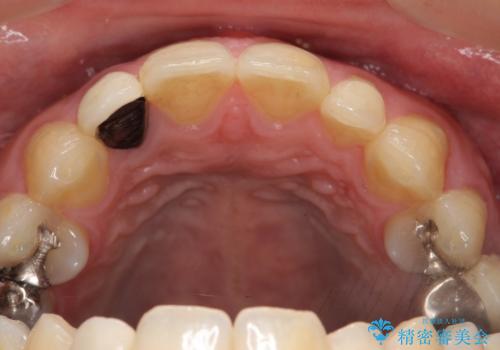

- 金属を使っていない被せ物に替えたいといらっしゃった方の症例です。

再根管治療終了後、オールセラミッククラウンによる補綴を行いました。

- オールセラミッククラウン(スペシャル)…¥130,000、仮歯…¥10,000、ファイバーコア…¥20,000、精密根管治療費別途費用は治療当時の料金となります